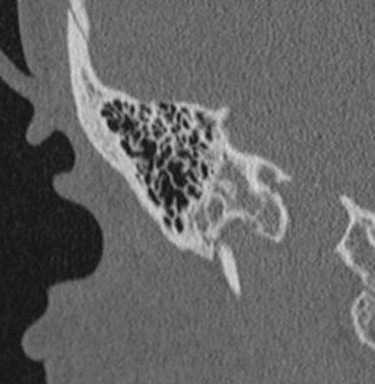

КТ. Дисплазия Мондини.

КТ. Полная аплазия лабиринта.

КТ. Расширение и укорочение полукружного канала.

КТ. Болезнь Меньера.

КТ. Водопровод в норме (стрелка).

КТ. Увеличенный водопровод (стрелка).

КТ. Хронический отит.

КТ. Хронический отит с кальцификацией барабанной перегородки.

КТ. Хронический отит с грануляциями на барабанной перегородке и эрозией стенки тимпанической полости.